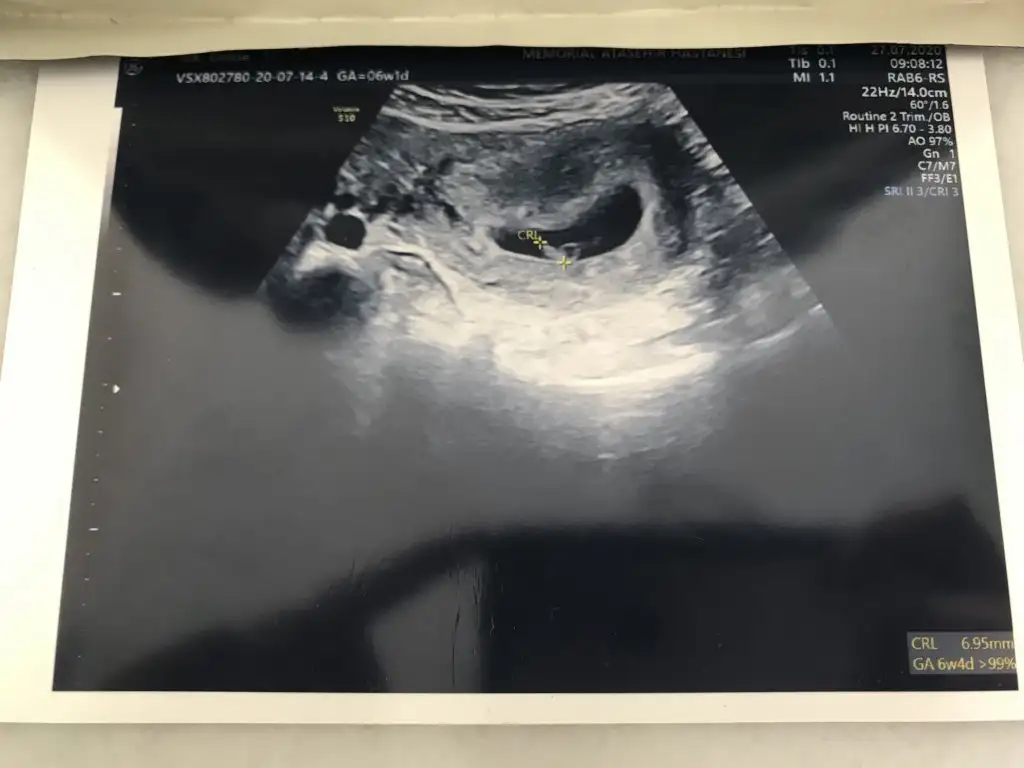

Baktım cnm sadece 11 ve 8 haftalık paylaşmışınız. Ve 15 haftalıgıMeraba kızlar bende 8 haftalik görüntü atmıştım tahmin yapan kişi erkek dedi şuan 15 haftaligiz ve oğlum olcak sizede örnek olsun ultrason resmimiz:)

Kız gibi ama en iyi 11 12 13 haftalar olmalıkarından ultroson 8+4 dü o zamanlar. tahminde bulunursanız sevinirim. teşekkürlerIkra meyra